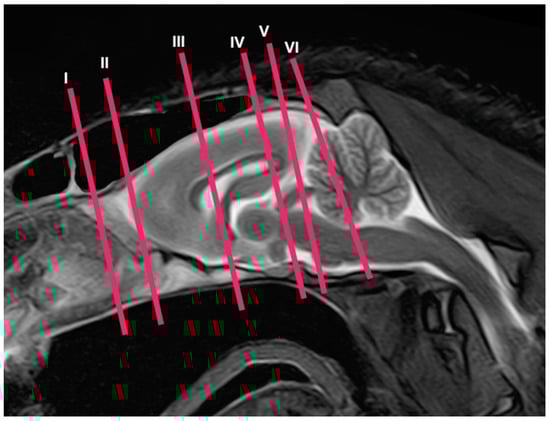

2.3. MRI Technique

3.2. Magnetic Resonance Imaging (MRI)